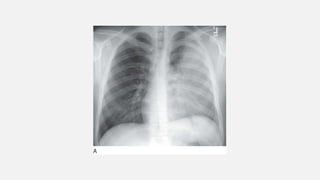

Perihilar “Bat-Wing” Consolidation Shows central consolidation with sparing of the lung periphery  Pulmonary edema  This pattern also may be seen with: • pulmonary hemorrhage • pneumonias (including bacteria and atypical pneumonias such as Pneumocystis jiroveci pneumonia [PCP] and viral pneumonia) • inhalational lung injury.

• #27 Perihilar “bat-wing” consolidation in pulmonary edema. A: Chest radiograph shows a distinct perihilar predominance of consolidation. The heart is enlarged. B: CT shows sparing of the lung periphery.